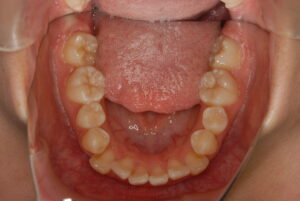

実際の症例紹介(20代女性/裏側ワイヤー矯正)

治療前

治療後

・主訴:八重歯と前歯の突出

・治療法:裏側からのワイヤー矯正(リンガル)

・治療期間:約1年半〜2年(目安)

・予想される副作用・リスク:装置装着後の違和感・疼痛、発音のしづらさ、一時的な咀嚼効率低下、ブラッシング不良によるむし歯・歯周病リスク など

※写真は代表的な症例です。口腔内の状態により治療法や期間は異なります。詳細は初診相談でご説明します。